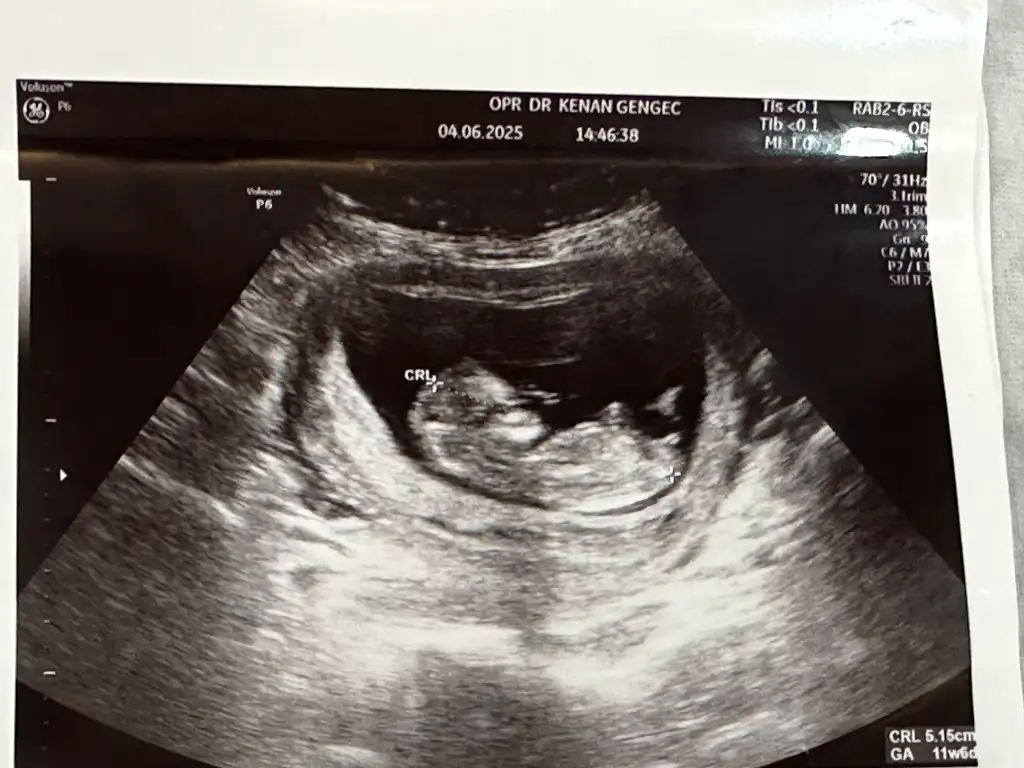

Bana da bakar mısınız lütfen biri 9 haftalık biri 6 haftalık karından ultrasonKese şekline göre erkek bence. Sağlıkla kucağınıza alın

Banada bakar mısnız lütfennnn çok merak ediyorum biri 9 haftalık biri 6 haftalık ultrason karından

Sizin de karından ultrason mıBanada tahmin yapar msnzzz

EvetttSizin de karından ultrason mı

kese şekline göre cinsiyet diye sorSordum canım erken diyor![]()